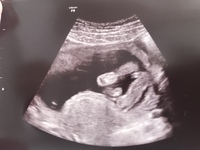

そして、胎児が成長してくると、 陰茎の根本に陰嚢が2つ確認できる ようになります。 女の子は陰茎のような目立つ外性器がないので判定が難しいのですが、 太ももの間に木の葉やコーヒー豆のような大陰唇が見え ます。 特徴がつかみにくい女の子ですが、妊娠週~24週 (妊娠6ヶ月から7ヶ月)頃になると、赤ちゃんのお尻を下からのぞいたような以下の画像のように、ようやく判明するケースが多いです。 この頃になると 女の子の赤ちゃんは、子宮と膀胱が2つの黒い点となっ